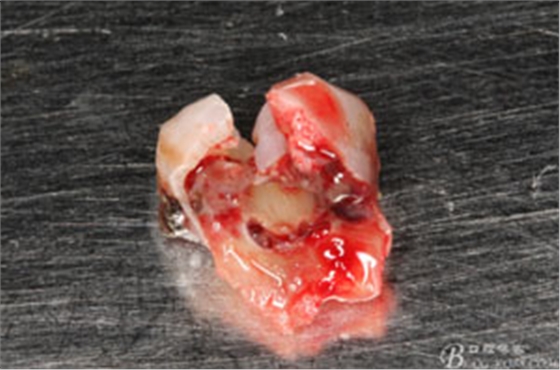

圖7.37牙冠碎裂。多生牙壓迫吸收程度嚴(yán)重。

圖8.拔除的37頰側(cè)的牙根完全被壓迫吸收完